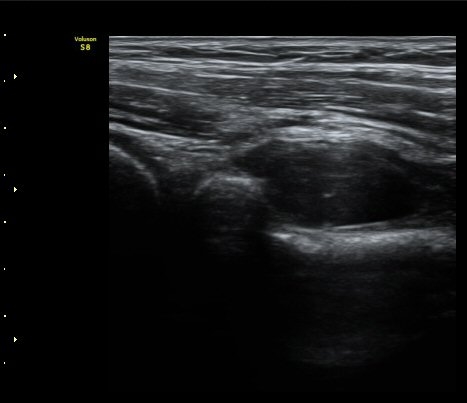

¼ÒµÎ Ⱦ´Ü¸é°Ë»ç¿¡¼­ ¿ä°ñ½Å°æ Èİñ°£½Å°æÀÌ Á¤»óÀûÀ¸·Î °í³ªÂûµÈ´Ù(±×¸² 1).